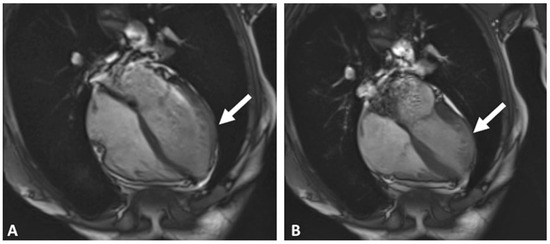

Pacemaker implantation via the femoral vein has been described since the 1980s. This technique is not very well known, but may be useful in some circumstances. We describe a case of a patient with sinus dysfunction without superior venous access, in...